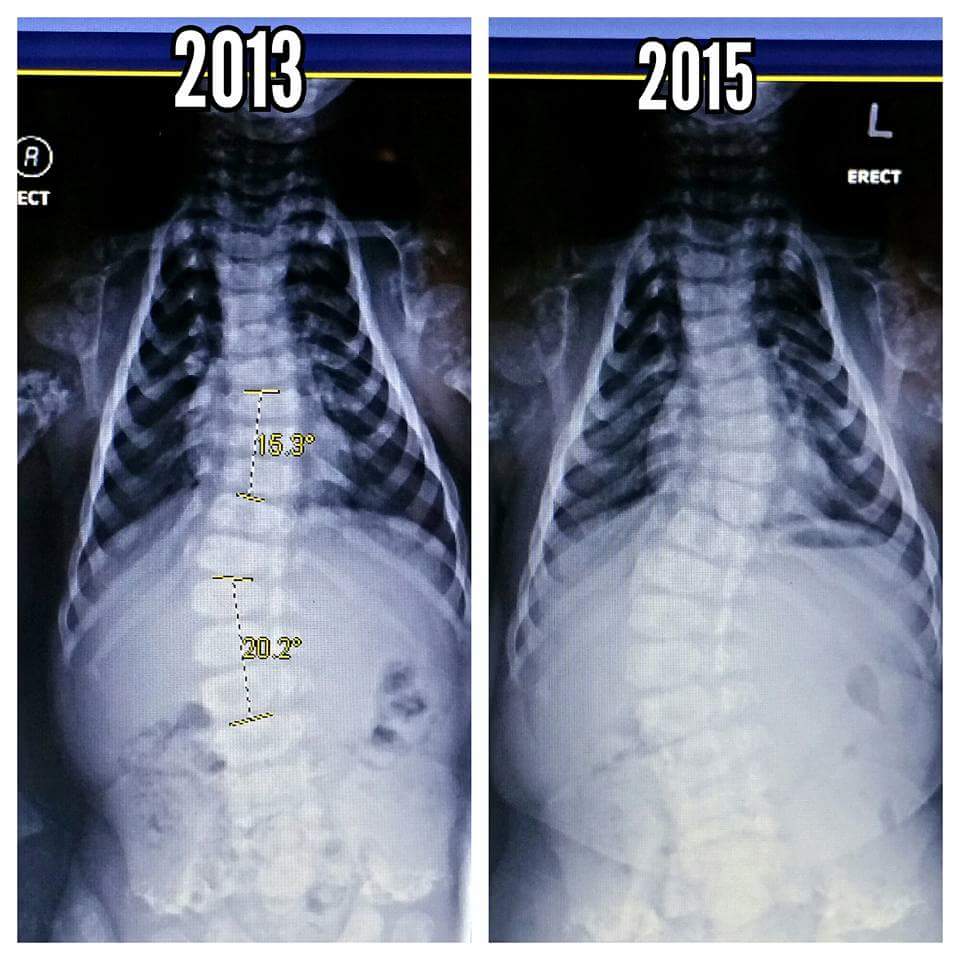

Levi's bending spine, Ocean Springs Hospital